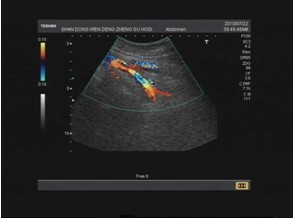

入院后化验检查示:D-dimer:584ug/L;予右胫骨结节骨牵引、注射用低分子肝素钙 5000iu 皮下注射 QD配合应用红花注射液 20ml+生理盐水 250ml 静滴 QD治疗三天后,患小腿出现肿胀、疼痛,踝过度背屈试验(Homans征)阳性,行右下肢静脉彩超示:考虑右侧腘静脉不全血栓形成(如图1)。暂停手术后嘱患者绝对卧床休息, DVT发病1~2周内最不稳定,栓子极易脱落,需绝对卧床休息,床上大小便;反复叮嘱患者及其家属切忌使患肢受压,忌做热敷,注意患肢保暖,绝不可按摩患肢或做运动;患肢下放软垫以抬高其至20°~30°,以利静脉回流,减轻水肿、疼痛。改用注射用低分子肝素钙(4100u)(速碧林) 皮下注射 QD配合应用疏血通注射液 4ml+生理盐水 250ml 静滴 QD。两天后复查D-dimer示:927ug/L;四天后再次复查D-dimer示:487ug/L,复查右下肢静脉彩超示:考虑右侧腘静脉陈旧血栓形成(如图2 )。科室内集体讨论后认为估计患者能够耐受手术,发生血栓脱落致严重肺栓塞的可能性较小,于两天后在硬膜外麻醉下行切开复位股骨近端锁定板内固定术。术后继前一般治疗,续用注射用低分子肝素钙(4100u)(速碧林) 皮下注射 QD配合应用疏血通注射液 4ml+生理盐水 250ml 静滴 QD。术后第十二天再次复查彩超回示:右髂外、股、腘静脉未见明显异常(如图3);复查D-dimer示:220ug/L。患肢肿胀也明显消退。于术后两周时拆线出院。

图2:考虑右侧腘静脉陈旧性血栓形成

图3:右侧腘静脉未见明显异常